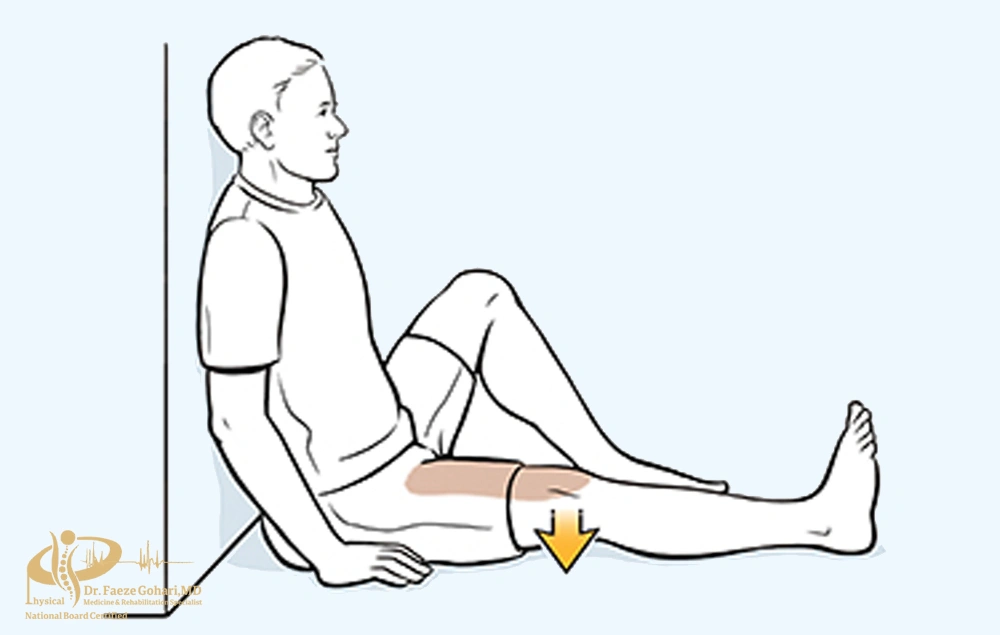

تمرین انقباض ایزومتریک عضله چهارسر ران

در حالت نشسته یا درازکش، زانو را صاف نگه دارید و عضله جلوی ران را برای ۵ ثانیه منقبض کنید، سپس رها کنید. این حرکت را ۱۰ بار در هر پا انجام دهید.